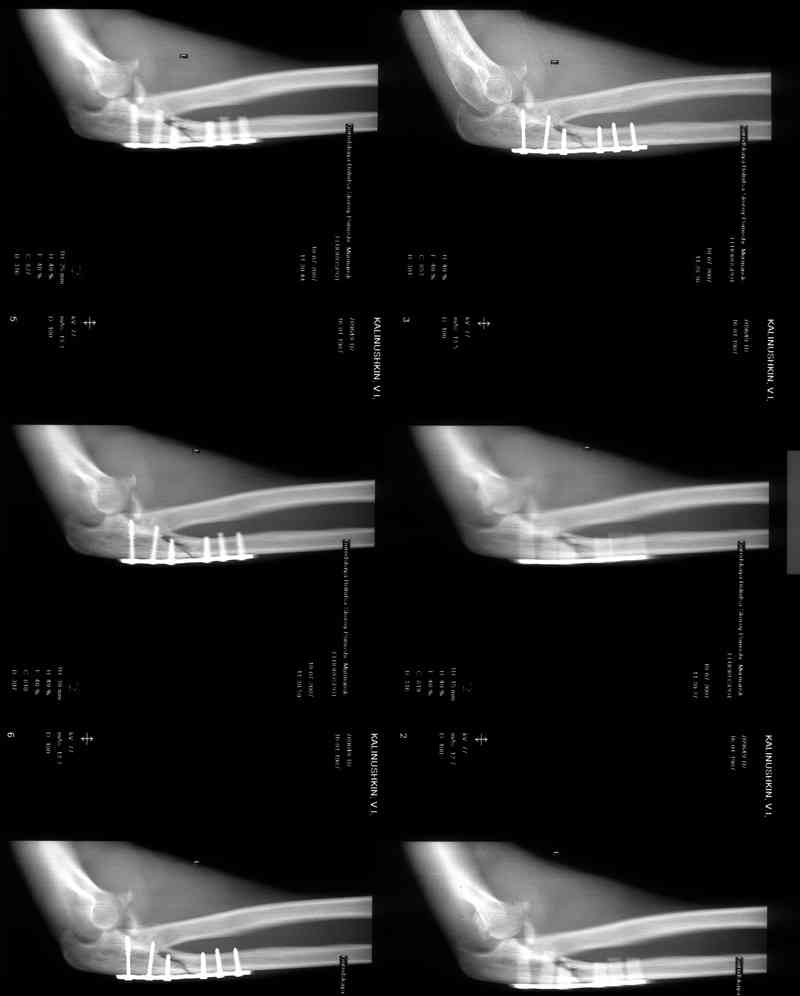

Re: Несросшийся перелом локтевой кости, подвывих предплечья кзади.Перелом венечного отростка. Состояние после резекции головки лучевой. Травма 4 мес. назад.

Был выполнен МОС локтевой пластиной,

Иммобилизация после операции 3 нед.Через 3 мес. на Rg несращение локтевой, подвывих предплечья кзади, осификаты в обл. венечного отростка.

Больной наблюдался в поликлинике,к нам попал

через 3 мес. Отмечается контрактура локтевого сустава, сгибание/разгибание 30/0/0.

МРТ у нас нет, сделаны томограммы.

1 восстановление венечного отростка: подшивание наибольшего фрагмента к локтевой кости вместе с передней капсулой см картинку

2 протезирование головки лучевой кости

3 интраоперационная оценка стабильности принцип см картинку

4 при наличии нестабильности восстановление соответствующей связки учитывая длительный срок с момента травмы возможно будет необходимо использование сухожильного аутотрансплантата

5 интраоперационная оценка стабильности принцип см картинку

6 при сохранении нестабильности трансфиксация локтевого сустава, после удаления спиц шарнирный ортез на 6 мес, при необходимости с ограничением разгибания

7 фиксация перелома локтевого отростка с помощью 4,5 DCP и стягивающего винта